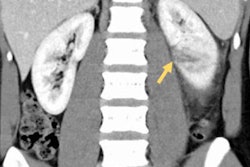

Sandhu and colleagues compared the diagnostic performance of digital tomosynthesis with that of ultrasound, using MDCT as the reference standard. The study included 66 patients who were either suspected of having kidney stone disease or had a history of recurrent disease; of these, 41 had urolithiasis and 25 had nonrenal causes of abdominal pain.

In the 41 patients with urolithiasis, MDCT found 121 stones (105 renal, 14 ureteric, and two vesical), most of which were smaller than 5 mm.

The average overall sensitivity of digital tomosynthesis for identifying kidney stone disease was 50% (p < 0.001), while the sensitivity of ultrasound was 50.4% (p = 0.005). As for identifying renal stones, digital tomosynthesis had a sensitivity of 47.1% and ultrasound a sensitivity of 50.9%; for ureteric stones, sensitivity was 74.9% with digital tomosynthesis and 39.2% with ultrasound.

Although the results did not show a statistically significant difference between digital tomosynthesis and ultrasound for diagnosing urolithiasis, the researchers did find that digital tomosynthesis performed better than ultrasound when it came to ureteric stones, suggesting that the modality may be preferred for the initial evaluation of these patients.

"Among the 14 ureteric calculi, the majority were in the mid ureter, which is technically the most difficult part of the ureter to examine on ultrasound as it is generally obscured by overlying bowel gas shadows," the group wrote. "The diagnostic accuracy of digital tomosynthesis in detecting ureteric calculi was relatively improved as it removes the overlying structures [and] enhances local tissue separation ... which allows for better visualization of calculi in the ureter."